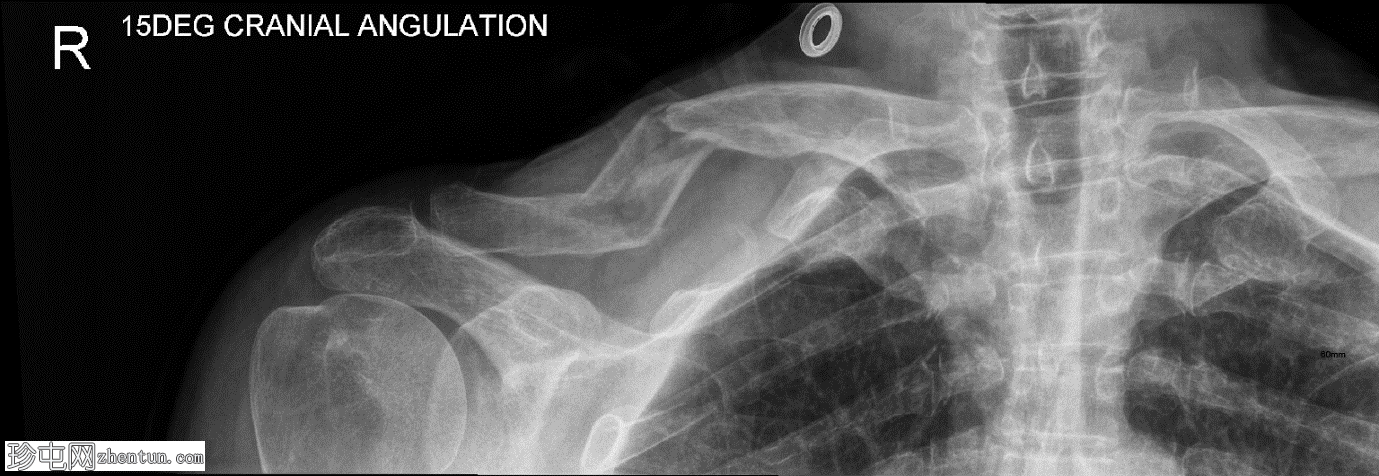

斜位

右侧锁骨中段呈Z形粉碎性骨折,近端内侧骨折块向上移位,远端外侧骨折块向下移位,内侧骨折处软组织轻度膨出。

可见衣物痕迹覆盖锁骨内侧区域。肩锁关节和胸锁关节保存完好,胸腔内未见相关肋骨骨折或气胸。

锁骨粉碎性骨折提示高位损伤机制。在某些情况下,锁骨可能断裂成多个呈之字形的碎片,而非简单的横向断裂。由于胸锁乳突肌和肩胛带肌肉的强烈反向拉力,这种模式通常会导致明显的位移和缩短。